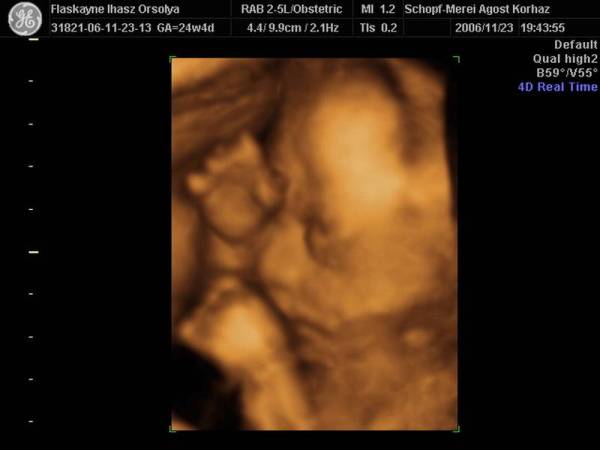

27.héten(Nagyon sokat változott,husis)